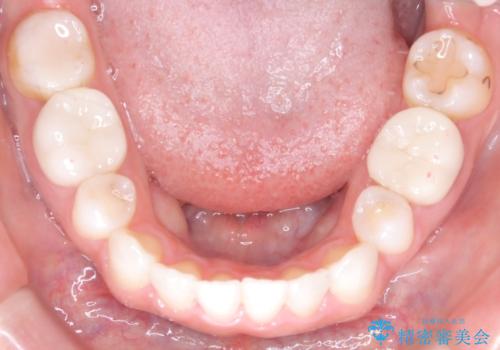

- 上下の歯の中心(正中)のズレと、口元の見た目を気にされて来院されました。精密な検査の結果、咬み合わせのバランスを整えながら、正中線を一致させる治療が必要と判断。患者様のご希望に合わせ、透明で目立ちにくいインビザライン(マウスピース矯正)による治療計画を立案しました。歯列全体を奥(遠心)へ移動させるためにゴムかけを併用。さらに、見た目を改善するため、既存の金属の被せ物をセラミッククラウンに交換することも治療計画に組み込みました。

今回の矯正治療では、透明なマウスピース型の装置インビザラインを使用しました。歯列を奥へ動かす遠心移動の効率を高めるため、患者様ご自身にゴムかけも行っていただきました。この併用によって、歯をより正確かつスムーズに動かすことができ、上下の歯の中心である正中線を一致させることが可能になりました。また、治療の最終段階では、以前から入っていた金属の被せ物を、天然歯に近い色合いのセラミッククラウンに交換。矯正治療と審美治療を組み合わせることで、機能的な咬み合わせの改善に加え、金属が見えない、より自然で美しい口元を獲得していただけました。